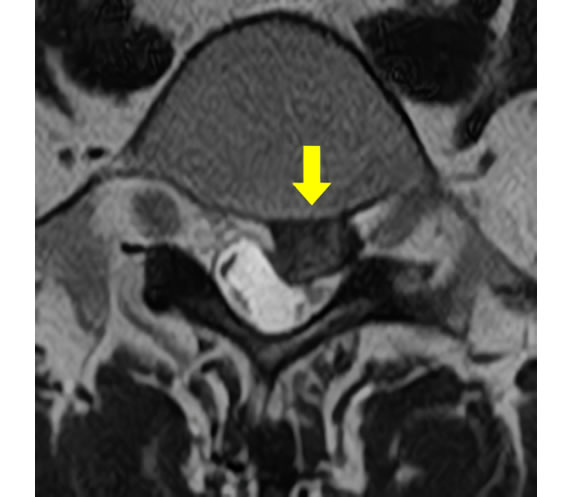

腰椎椎間板ヘルニアと腰部脊柱管狭窄症の違い

| 腰椎椎間板ヘルニア | |

|---|---|

| 椎間板のみが突出し、神経を圧迫した状態です。10~50 歳代に多いです。 | ![]() (腰椎を輪切り にした図) |